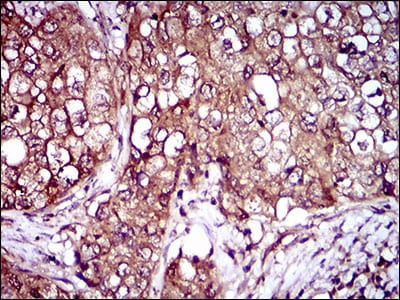

Immunohistochemical analysis of paraffin-embedded human ovarian cancer tissues using IL3RA mouse mAb with DAB staining.

Immunohistochemical analysis of paraffin-embedded human lung cancer tissues using IL3RA mouse mAb with DAB staining.